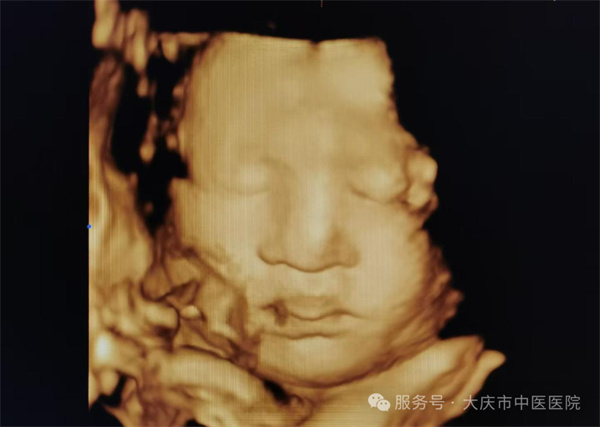

近日,大庆市中医医院超声医学科通过四维彩超筛查,为一位准妈妈做出了及时准确的胎儿发育健康提示。该孕妇为第二次妊娠,曾孕育一健康女孩,现孕23周,在超声医学科进行胎儿系统筛查时,当日值班医生,超声医学科副主任王双艳,经过一番认真细致的检查,发现胎儿存在左侧三度唇裂伴左侧牙槽突裂,其余胎儿结构未见异常。随即向孕妇及家属详细介绍唇腭裂的类型、程度及可能对胎儿出生后的影响,如影响外貌、进食、发音等,同时说明不同程度唇腭裂的治疗方法和预后情况,让孕妇对胎儿病情有全面、客观的认识。最后孕妇决定继续妊娠,足月剖产后证实了产前的诊断。截至目前超声医学科已诊断各型唇腭裂5例,均得到产后证实。

生育一个健康的宝宝是准妈妈们的最大心愿!因此四维彩超筛查十分必要。通过系统超声检查能够清晰显示胎儿颜面部的形态结构,可以实时动态观察到唇部和腭部的连续性,能直观呈现唇腭裂的部位、程度等情况,并且能清晰显示唇裂是单侧还是双侧,裂隙的大小等。让医生和家庭提前知晓胎儿情况,为是否继续妊娠等决策提供关键依据。有助于减少严重出生缺陷儿的出生,提高人口素质。 若确诊唇腭裂,医生可结合其他因素综合评估,为产妇选择更合适的分娩方式,保障分娩过程中母婴安全。诊断结果能协助临床相关科室制定出生后治疗计划,确保患儿出生后能及时得到多学科综合治疗。

大庆市中医医院四维彩超设备,为三星WS80A彩超诊断系统,具有极高的清晰度和分辨率。能360°全方位立体呈现胎儿表面畸形、内脏畸形和头面部畸形及宫内发育情况,如胎儿孕周、体重大小,预产期的估测,脐带血流及胎儿宫内缺氧的评估等,还有子宫动脉的超声评估,是应用于胎儿产前筛查、及完整记录胎儿宫内高清动态的先进超声设备。超声医学科以规范化的胎儿系统筛查标准服务于广大孕产妇,严格做到标准、规范、细致、认真。在此也提醒准妈妈们,要重视产前超声检查,以超声之“眼”,为“好孕”护航。